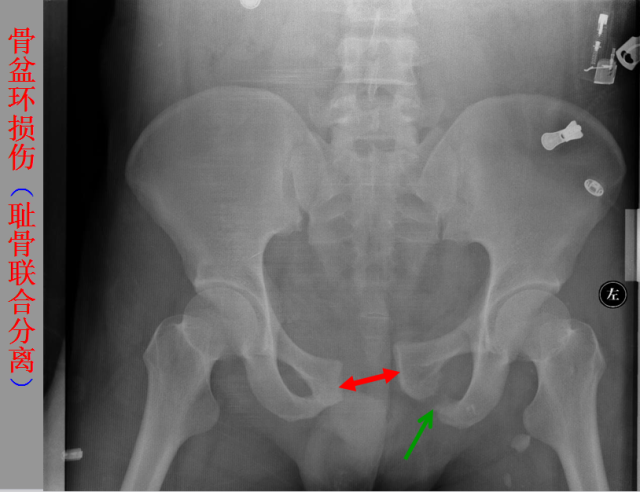

骨折篇

01

定义:骨折{Fracture}是指骨的完整性和连续性的折裂或粉碎。包括创伤性骨折、疲劳性骨折和病例理性骨折。 临床上以创伤性骨折*常见。